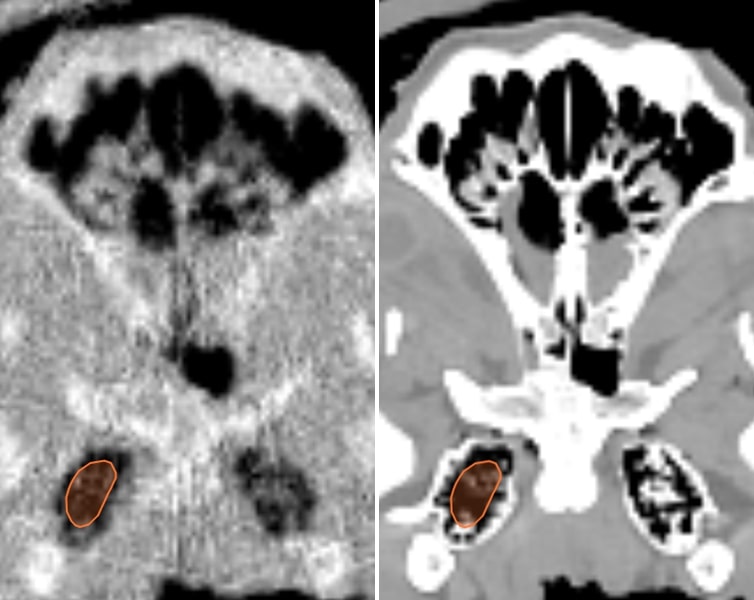

3.D. Comparison of pCT and x-ray CT for the pig’s head

Examples of regions for one slice each in three views of the pig’s head are indicated in Fig. 6, and RSP comparisons between the pCT and the three x-ray CT scans are in Table 3. A close up axial view of the tympanic bullae is shown in Fig 7, which illustrates that the tympanic bullae ROI encompasses a heterogeneous mixture of pneumatized cells separated by thin bony septa. The high and low dose horizontal CT RSPs are consistent within 0.5%. The vertical x-ray CT scan generally shows similar results, although with differences of 2% for brain stem and skull relative to the horizontal scans. Ignoring the RSP differences for sinus air, which are insignificant in absolute terms, the largest difference between pCT and x-ray CT is for the bullae, (-29% to -41%), followed by skull (-2.4% to -4.3%) and brain stem (-2.2% to -4.4%). All other RSP differences (n=24 for 8 tissues) range from -2.5% to +2.1% with a mean of -0.4%. With the exceptions of tongue and lens, the differences for these eight tissues are negative or zero.